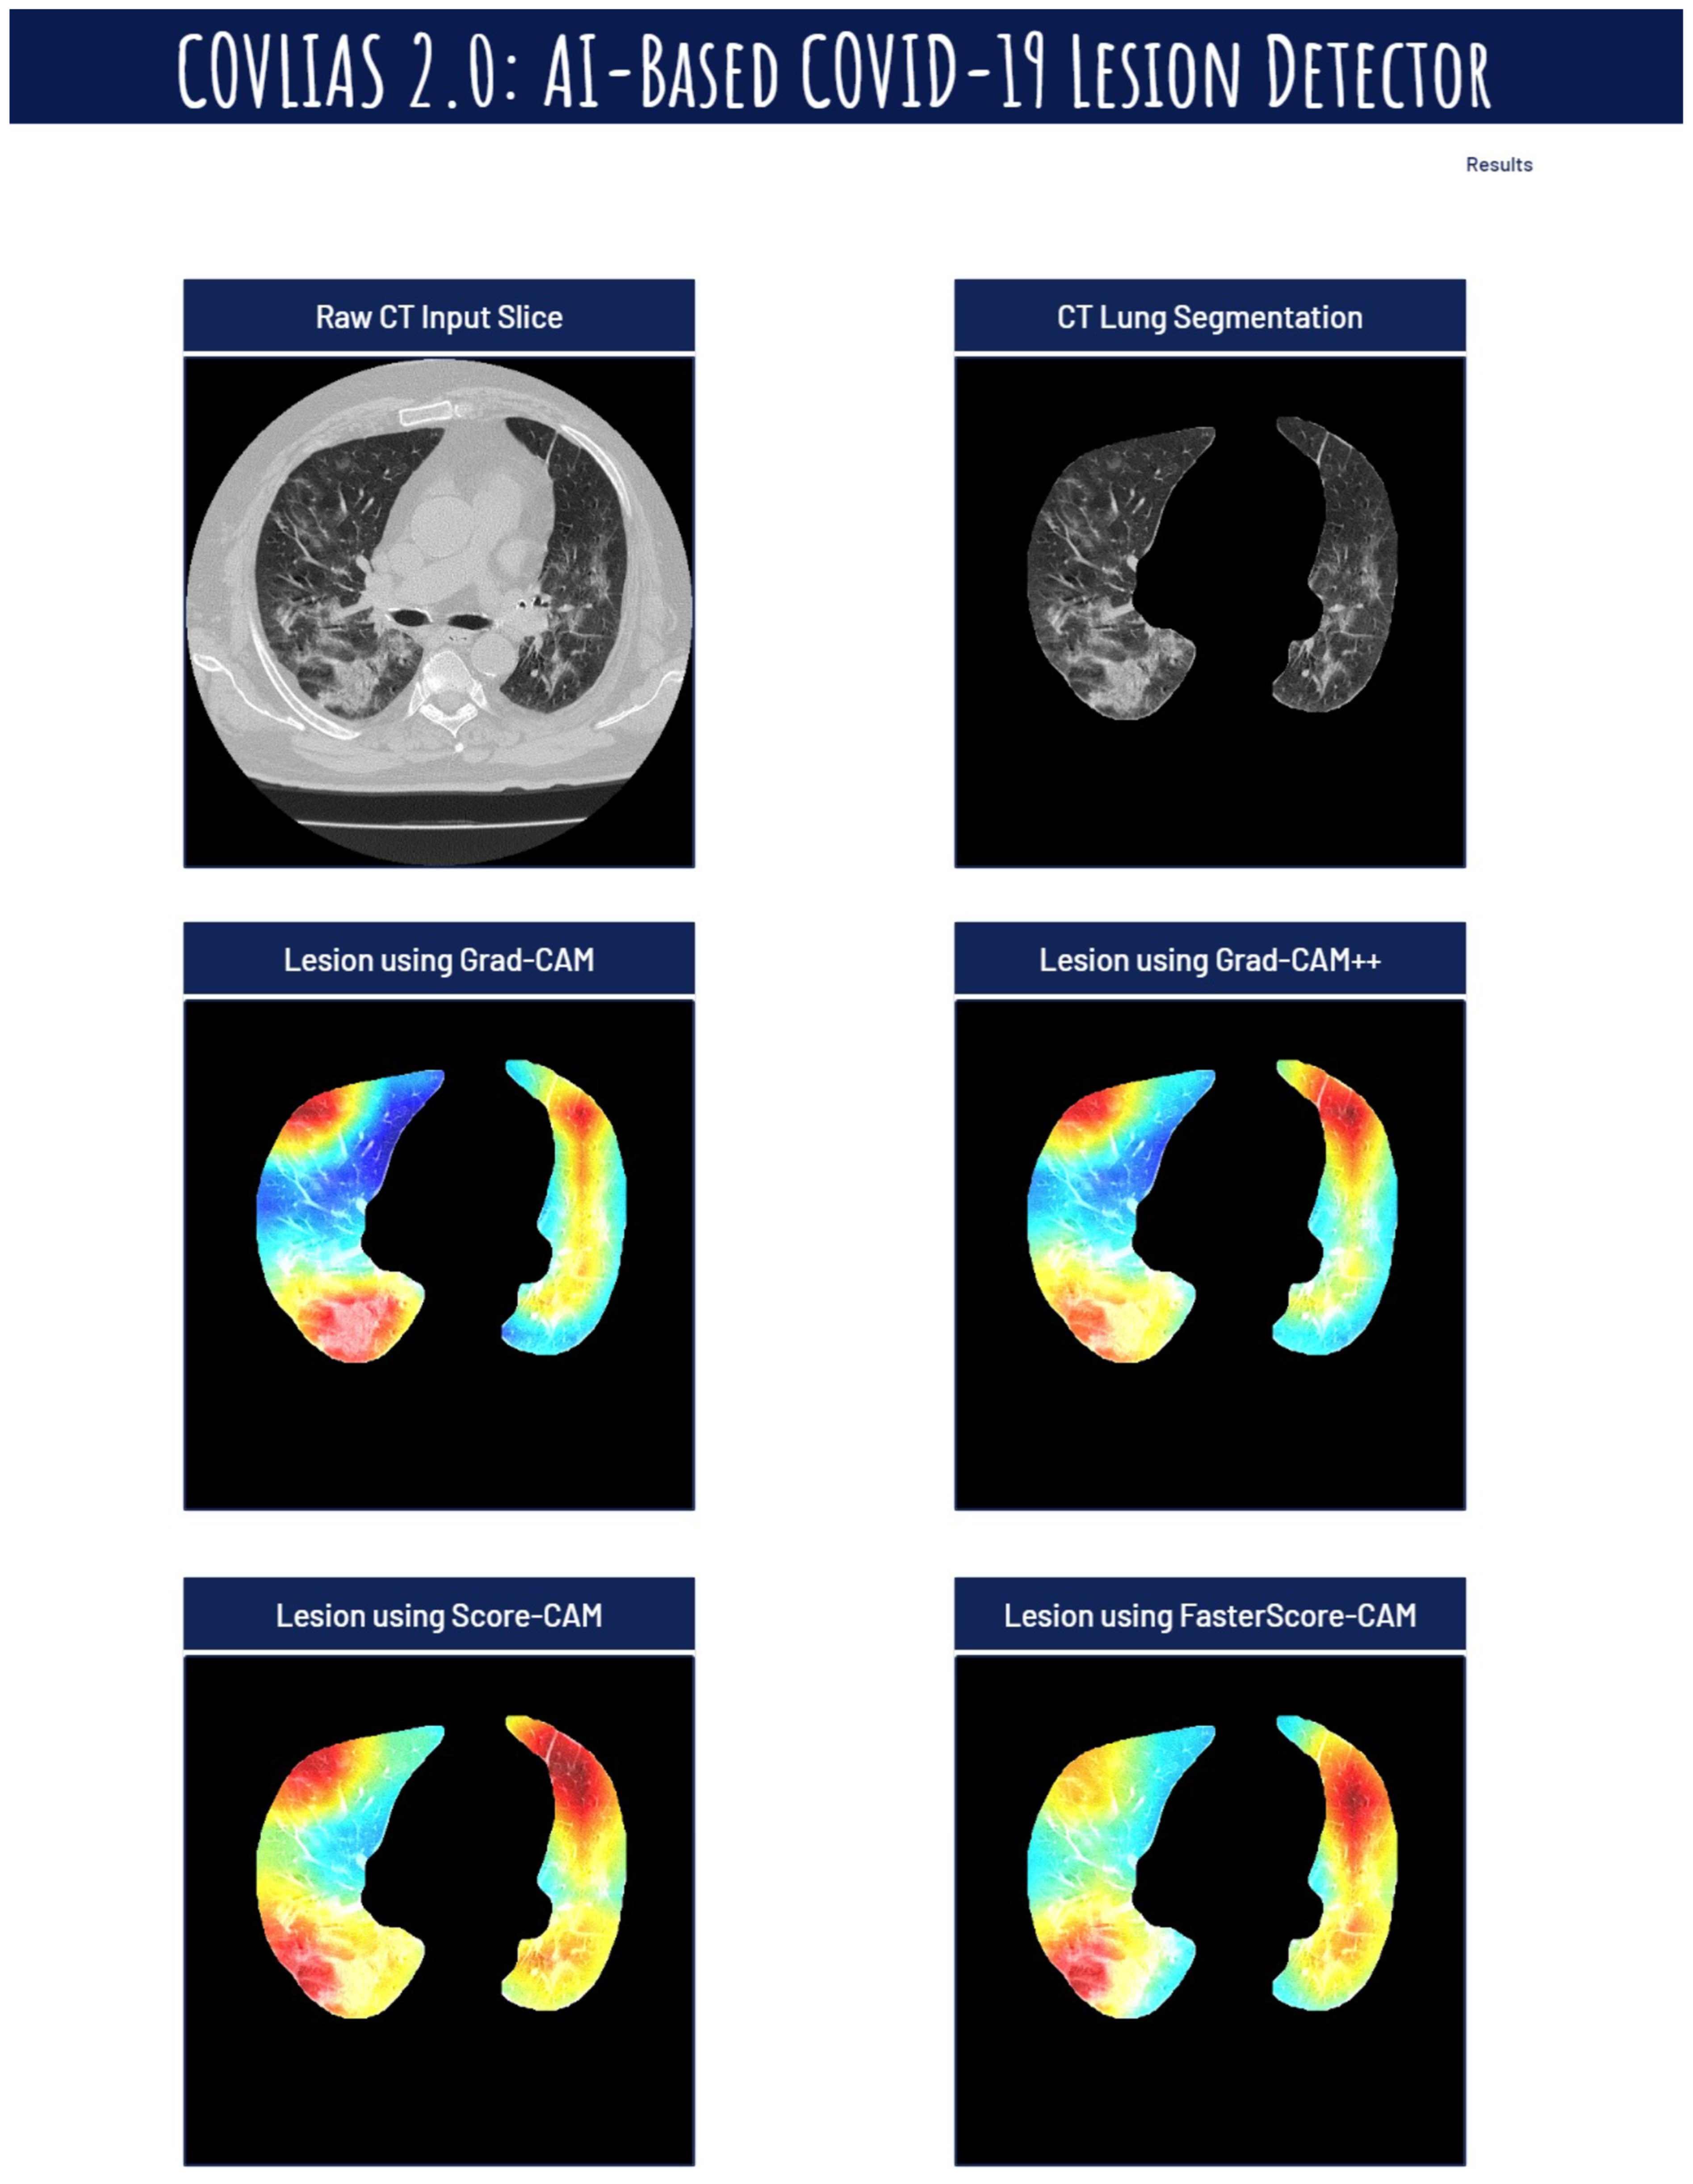

Visual Results Representing Lesion Using the Four CAM Techniques

4.1. Study Findings

4.4. A Special Note on Four CAM Models